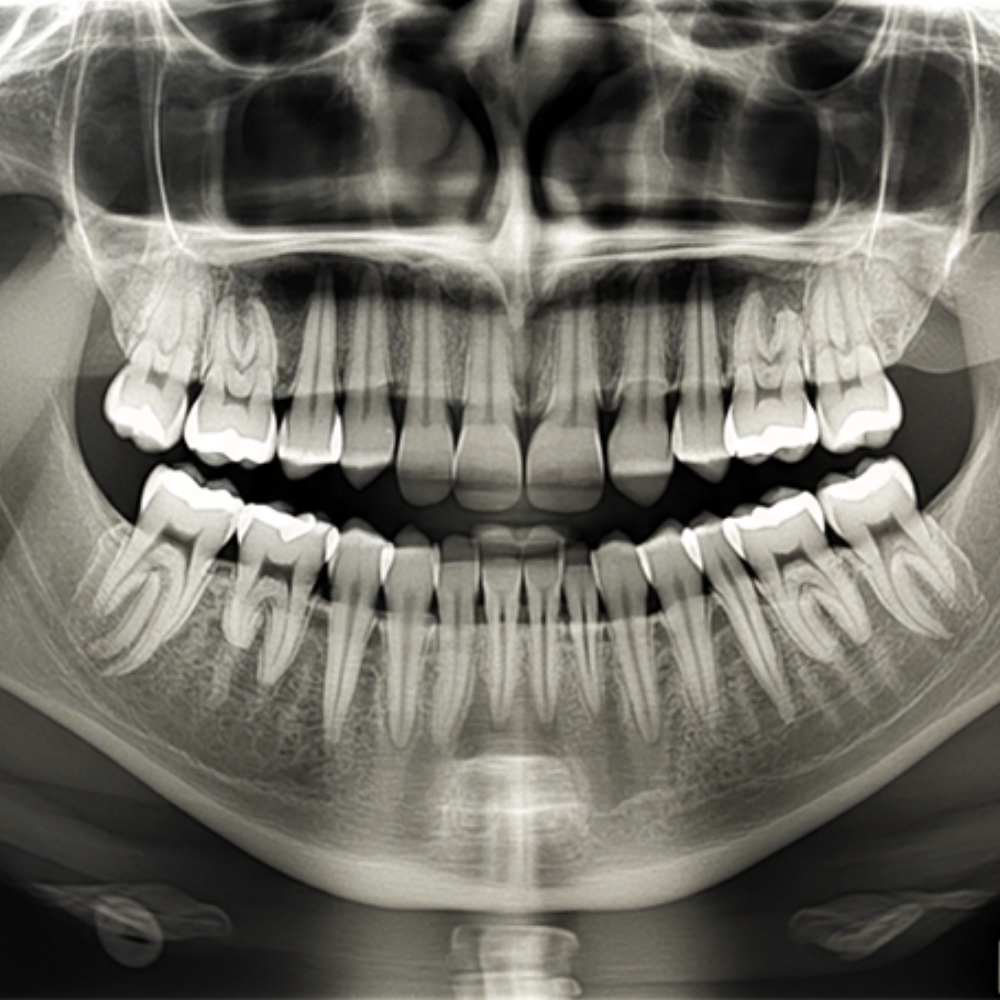

Fogászati röntgen

A fogászati elváltozások többsége hagyományos szájüregi vizsgálatokkal nem mutatható ki, ezért kiemelkedően fontos, hogy a röntgenfelvételek segítségével teljes képet kaphassunk a szájüreg egészének állapotáról.

A fogászati röntgenfelvétel nem csak komplex beavatkozásoknál, hanem az általános fogászati kezelések során is javasolt lehet. A digitális röntgen az egész fogsor állapotáról pontos képet ad. Segítségével kimutathatók a rejtett fogászati elváltozások is. A röntgen-felvétel leggyakrabban az alábbiakban lehet a segítségünkre:

- fogszuvasodás felderítésekor,

- bölcsességfog-gyulladás esetén, arcüreggyulladás esetén,

- fogínyvérzés, fogínysorvadás okainak kiderítéséhez,

- fogászati ciszták és gyulladásos gócok feltérképezéséhez,

- szájsebészeti beavatkozások előtt,

- fogszabályozást megelőzően,

- fogimplantációt megelőzően.